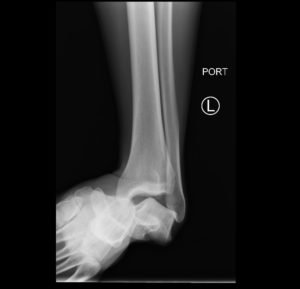

Subtalar dislocation is an unusual form of joint injury from high-energy trauma or athletic injuries. This case report describes a 22-year-old male who presented to the emergency department with left ankle pain after falling from his bicycle. Examination revealed significant deformity of the left foot and ankle. The foot pointed medially, and the bottom portions of the tibia and fibula were visible with the overlying skin intact. Radiographs confirmed left medial subtalar dislocation. There was no neurovascular compromise of the foot. The dislocation was successfully reduced under procedural sedation and the patient’s left leg was placed in a splint. He underwent post-reduction imaging and was instructed to remain non-weight-bearing and to follow up with orthopedics to discuss further management. The purpose of this report is to describe a case of a closed, medial subtalar dislocation and the approach to management.